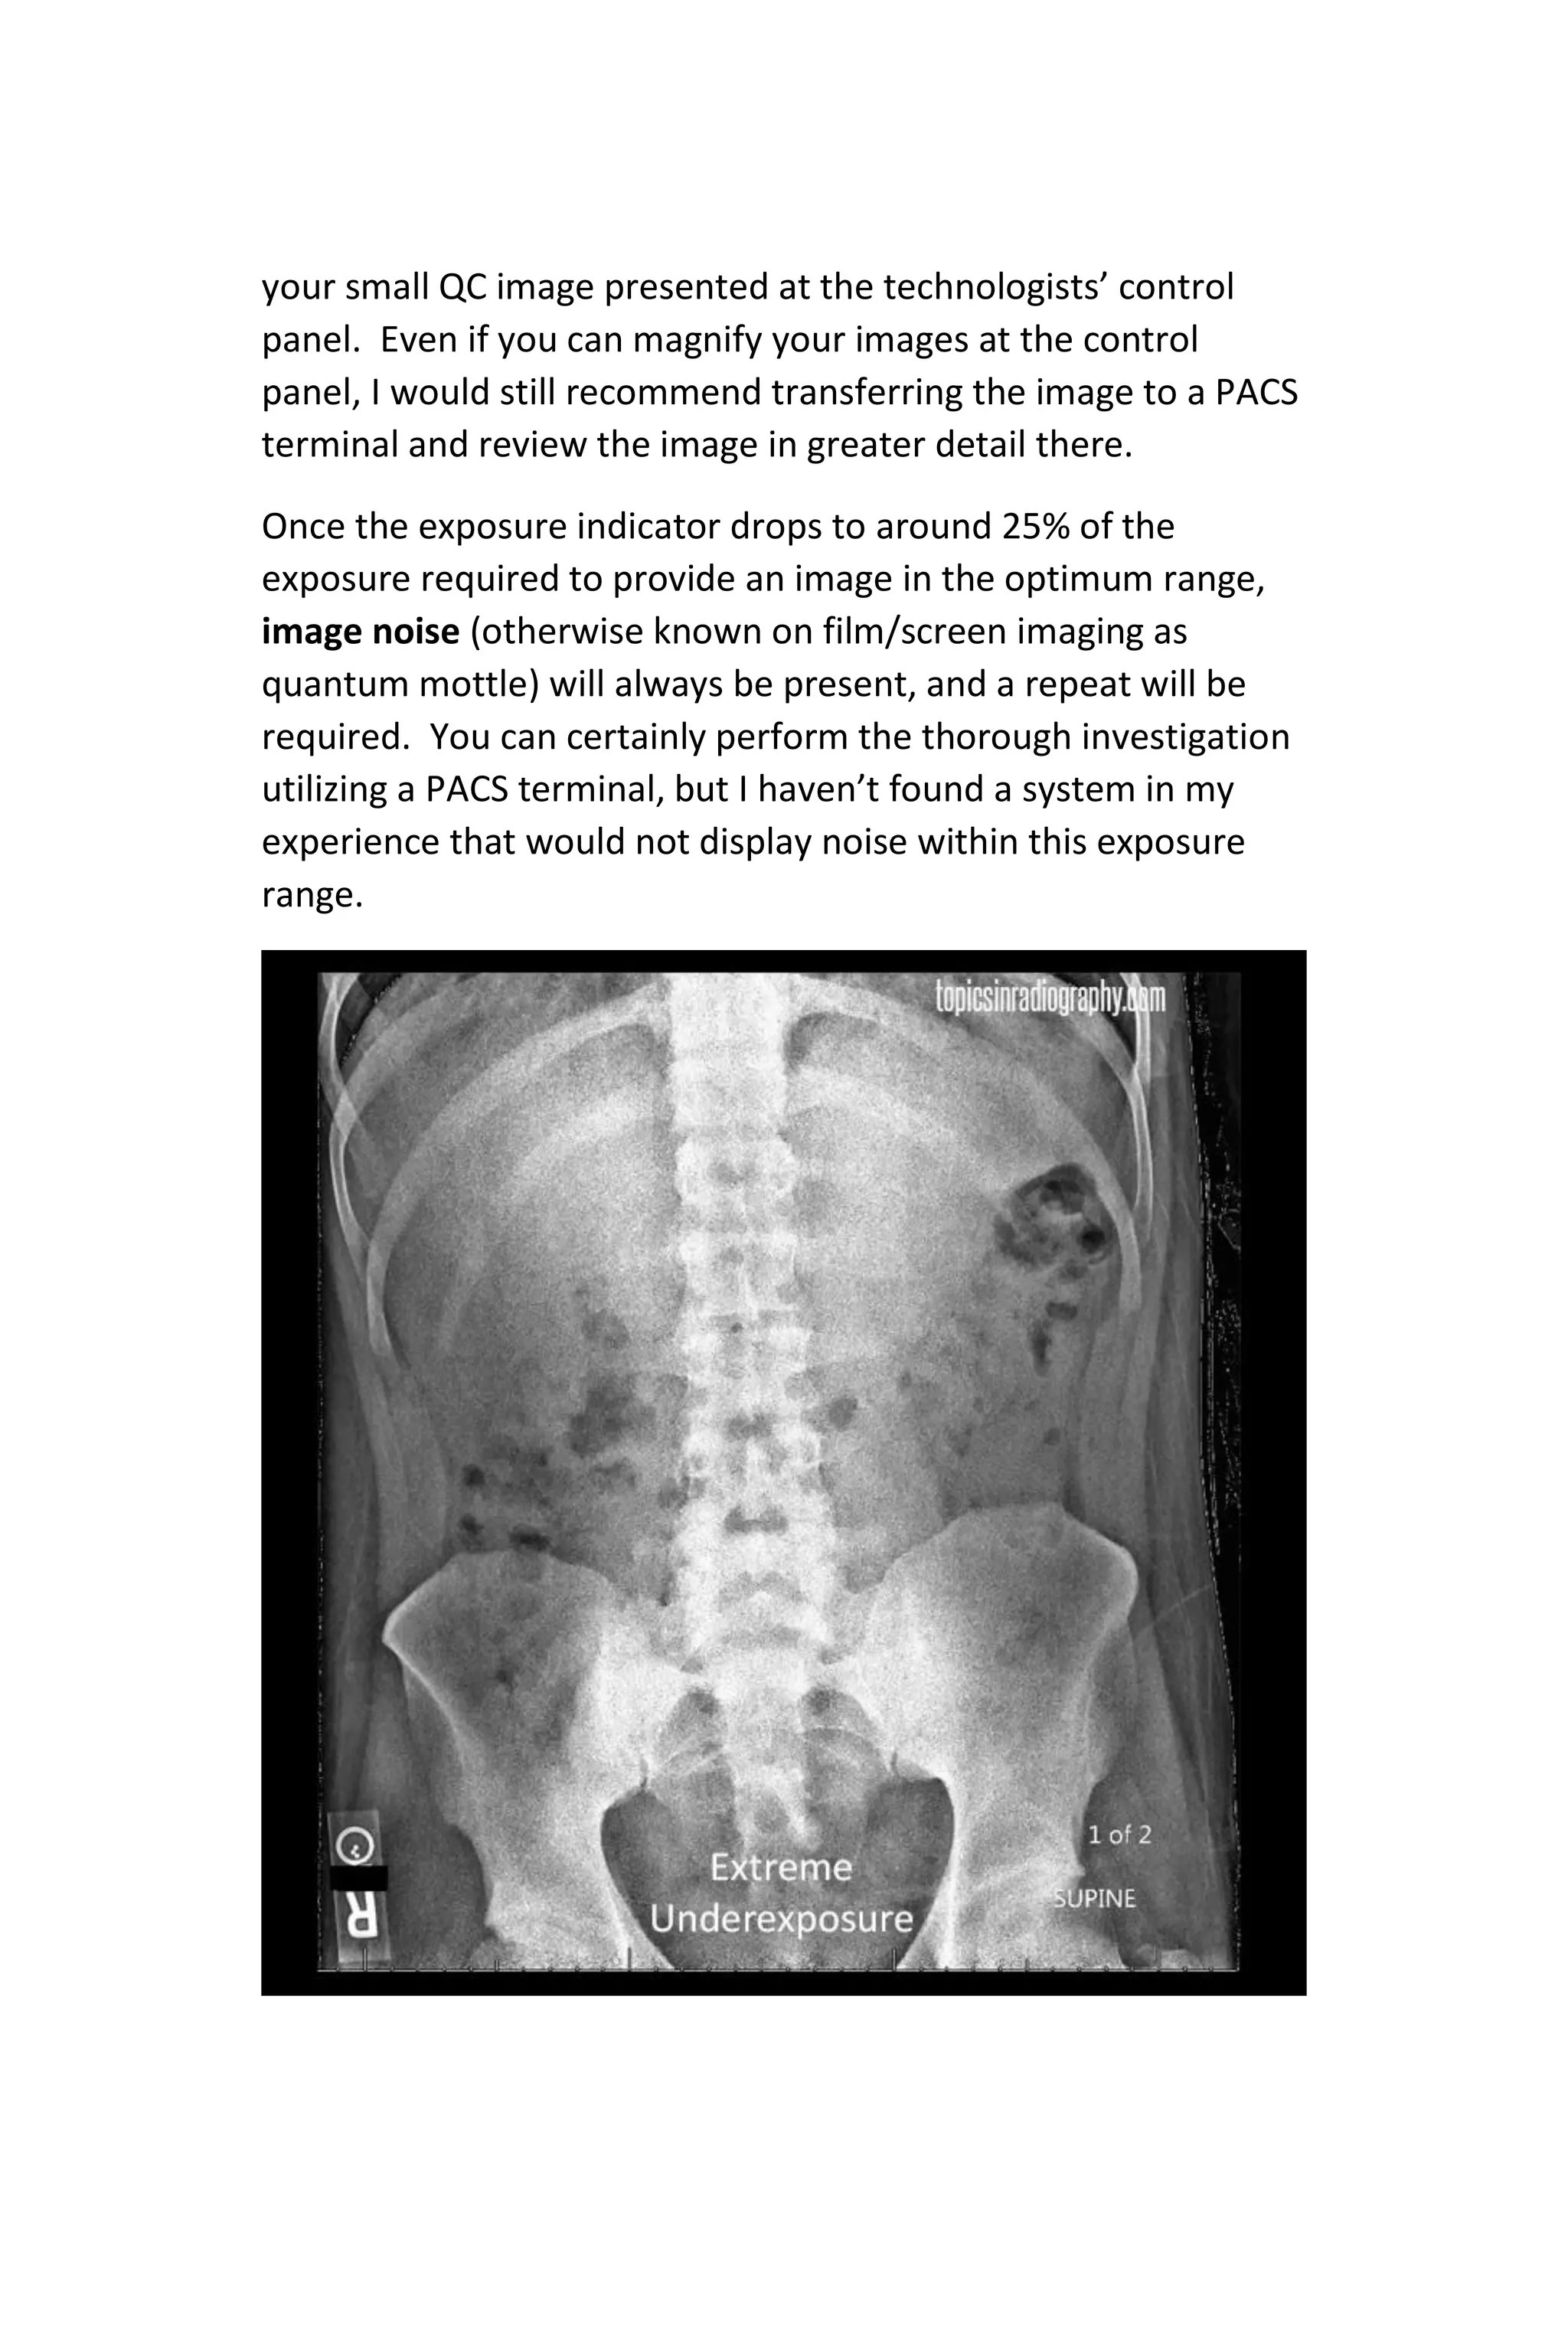

Once the exposure indicator drops to around 25% of the

exposure required to provide an image in the optimum range,

image noise (otherwise known on film/screen imaging as

quantum mottle) will always be present, and a repeat will be

required. You can certainly perform the thorough investigation

utilizing a PACS terminal, but I haven’t found a system in my

experience that would not display noise within this exposure

range.

Any image noise you see present on the low resolution monitor

during image QC will only be amplified for the radiologist, so as

a rule of thumb, consider a repeat of noise is obvious as in the

image above.